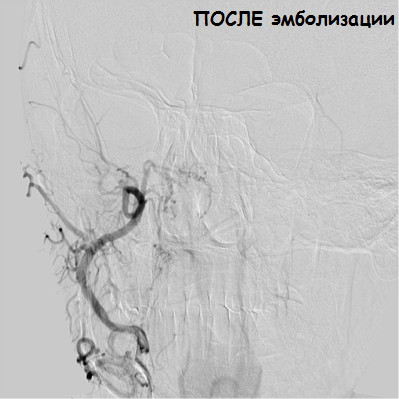

— Через бедренную артерию микрокатетер был введен в артерию, непосредственно кровоснабжающую опухоль, — комментирует ситуацию заведующий отделением РХМДиЛ Александр Евгеньевич Ванюков. — Артерия диаметром около 1 мм является ветвью верхнечелюстной артерии, и, на наш взгляд, безопаснее и эффективнее выполнять точную селективную катетеризацию и эмболизацию артерии, питающей опухоль, чем эмболизировать всю верхнечелюстную артерию. Мы выполнили суперселективную эмболизацию путем введения эмболизационного материала размером 700 нм, что привело к полному прекращению кровоснабжения опухоли.

На 2-е сутки после эмболизации отохирурги повторно открыли барабанную полость и на абсолютно сухом операционном поле смогли удалить остатки опухоли и провести реконструктивную операцию с целью улучшения слуха. Послеоперационный период без осложнений, пациентка выписана на 5-е сутки.